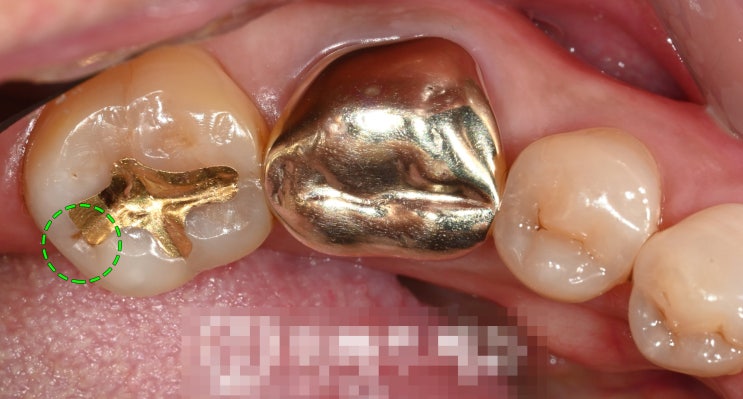

신촌역치과 정기검진의 중요성 다수의 충치 재발, 인레이, 신경치료

안녕하십니까, 대표원장 조민기입니다. 여러분들께서는 정기검진 을 받으신지 얼마나 되셨나요? 많은 분들...